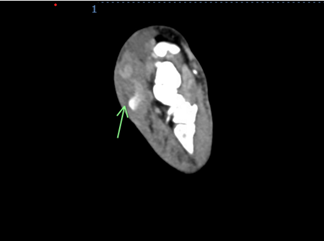

A 73-year-old man with history significant for paroxysmal atrial fibrillation on apixaban underwent percutaneous coronary intervention (PCI) of the left anterior descending artery via transradial access. The patient was discharged on clopidogrel, atorvastatin, carvedilol, isosorbide mononitrate, losartan, and apixaban. Ten days later, the patient presented with swelling in the right hand, wrist, and forearm (Figure 1). Doppler arterial ultrasound (US) showed an outpouching measuring 3.9 cm x 2.8 cm in the distal radial artery with a neck measuring 2 mm (Video). A radial artery pseudoaneurysm (PSA) was diagnosed. Before the surgical team could intervene, the PSA ruptured (Figure 2). Computed tomographic angiogram (CTA) with contrast showed 1.5 cm x 1.5 cm PSA with contrast extravasation laterally and into the dorsal soft tissues of the wrist/distal forearm consistent with hematoma and PSA rupture (Figure 3A, B). The patient underwent successful evacuation of hematoma and reconstruction of the radial artery.